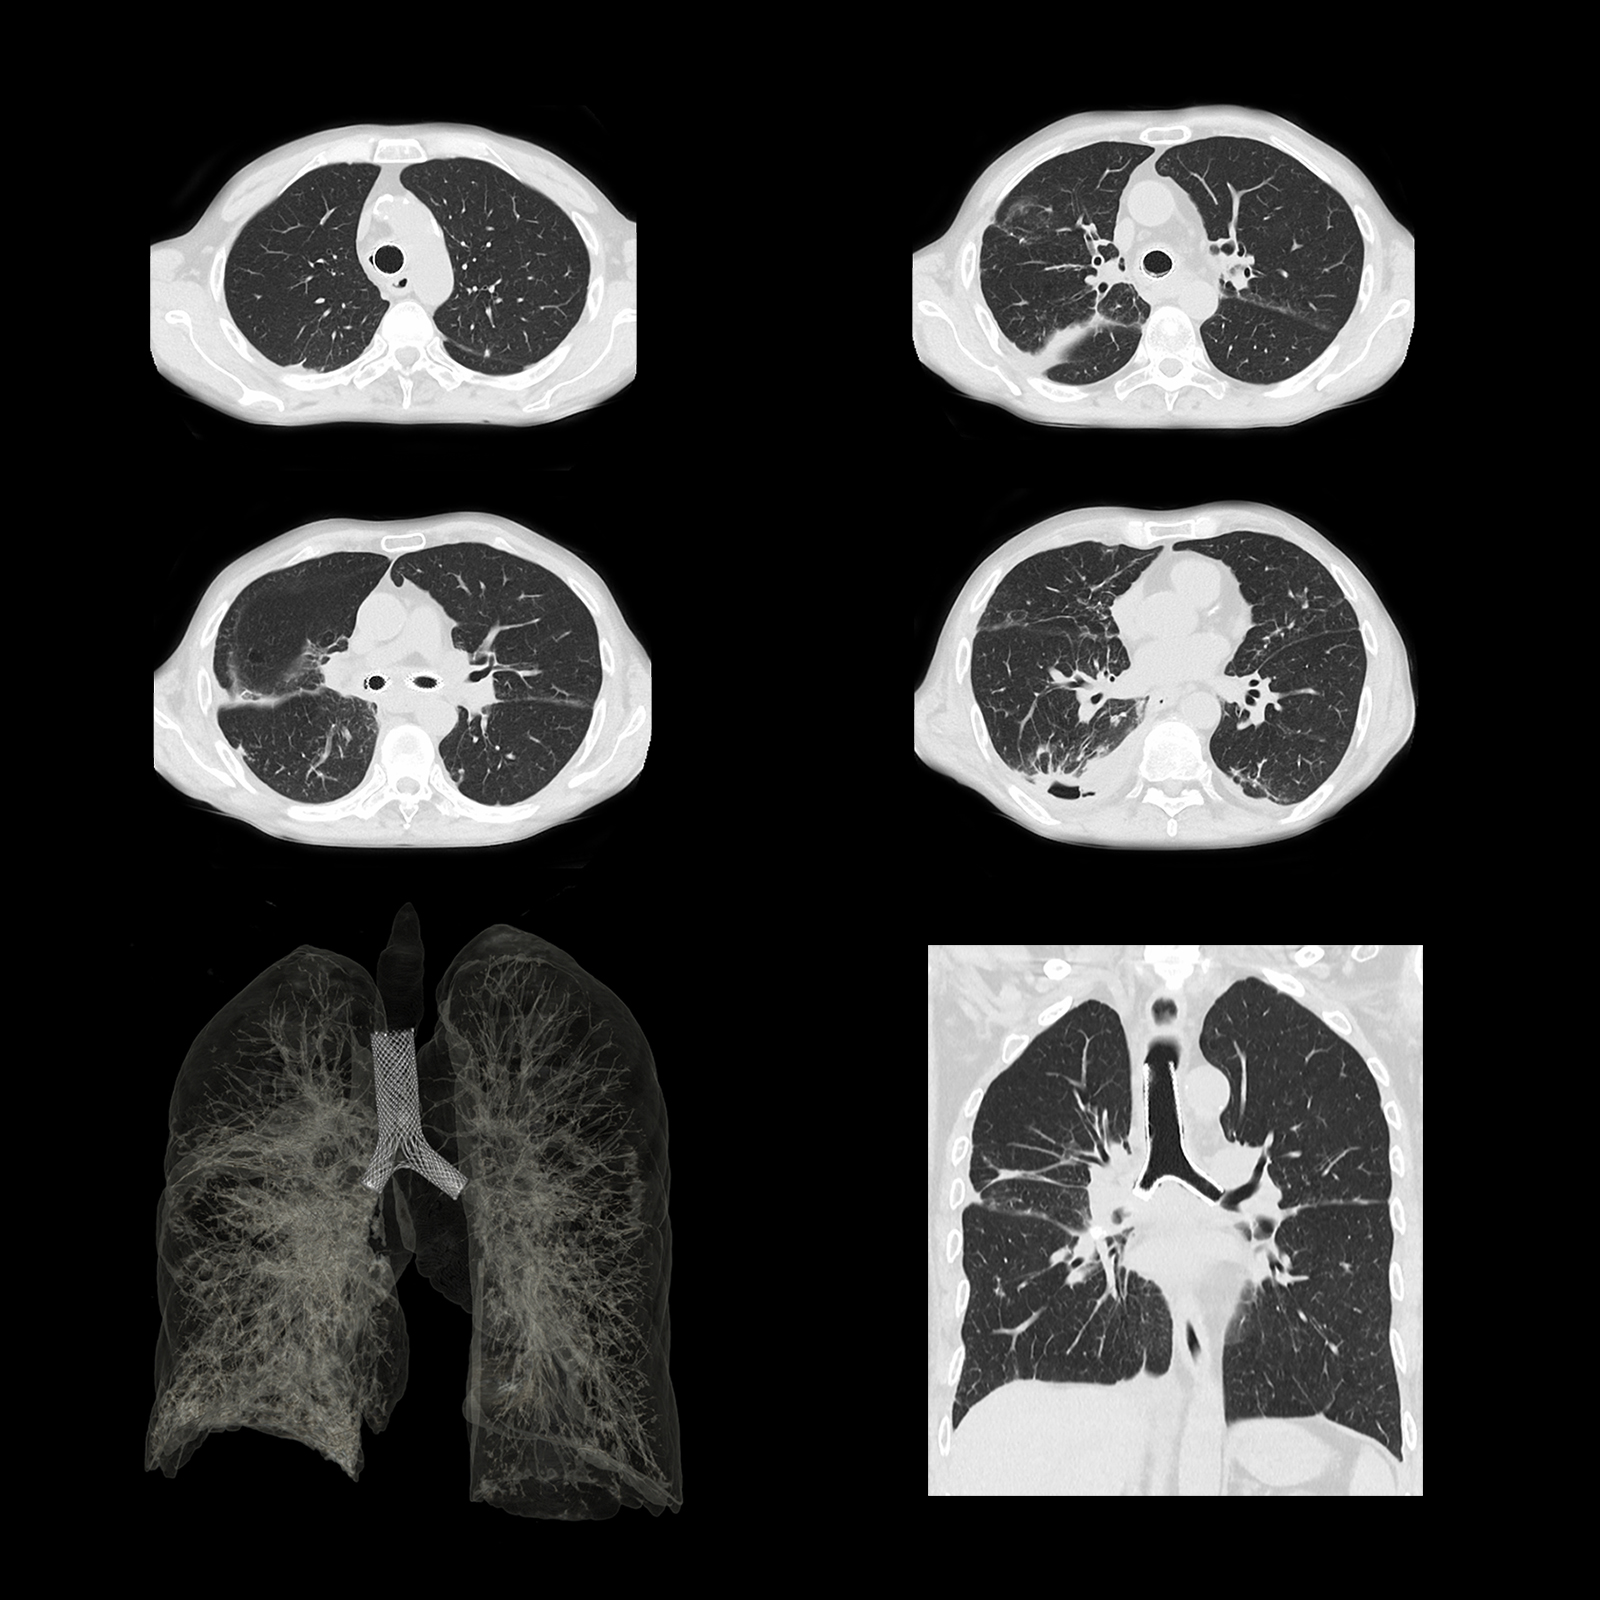

Расширенный интеллектуальный модуль Clear-IQ Engine (AiCE)

КТ-реконструкция, в которой используются инновации глубокого обучения, чтобы соответствовать пространственному разрешению и малошумным свойствам усовершенствованных итеративных реконструкций на основе моделей для получения высококачественных изображений без ущерба для скорости или дозы.

- Малый шум

- Естественная текстура изображения

- Четкое высококонтрастное разрешение

- Четкая низкоконтрастная детектируемость